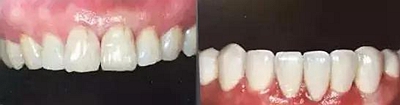

上下前牙正面影像

構(gòu)圖包含4-6顆前牙,中切牙為對焦中心

采用黑背景

拍攝比例:1:1.8,光圈f38,快門速度1/125,閃光強度M/4

上下前牙側(cè)面影像